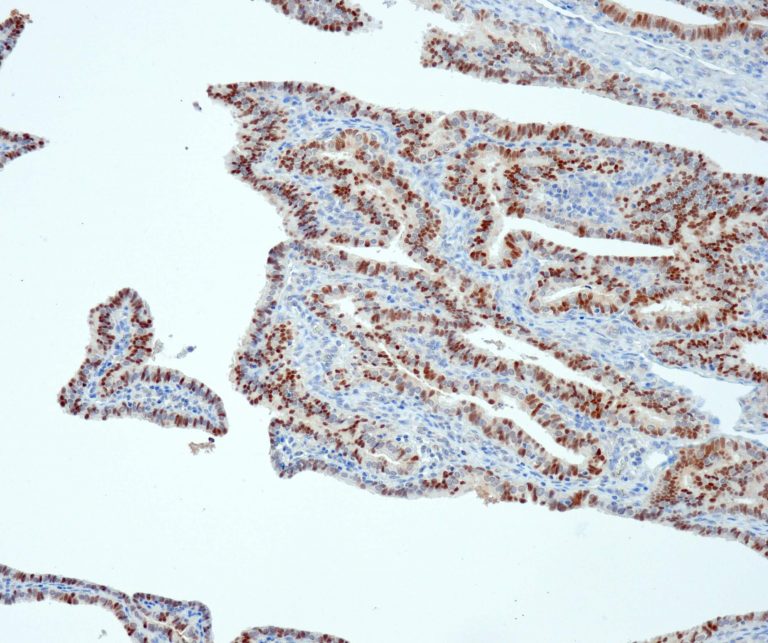

Gastrointestinal (GI) Pathology

Breast Pathology

Gynecological Pathology